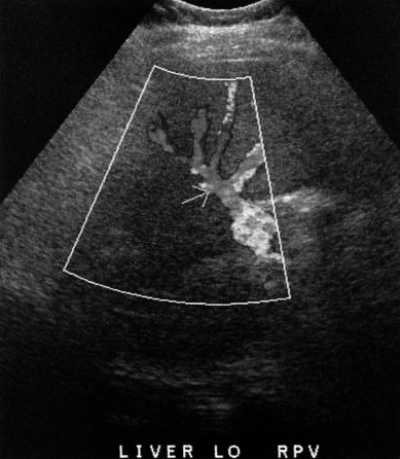

При исследовании портосистемных анастомозов основной задачей УЗИ является оценка проходимости шунтов с помощью методов цветовой, спектральной и, возможно, усиленной допплерографии. УЗИ помогает оценить состояние TIPS, однако спленоренальные, мезокавальные и портоковальные анастомозы, как правило, закрыты газами кишечника (фото 9).

Фото 9. Портокавальный шунт. А – цветовая допплерограмма показывает проходимый портокавальных шунт между дистальным отделом воротной вены и нижней полой вены (IVC). В – спектральная допплерограмма демонстрирует кровоток, направленный по шунту от печени в сторону нижней полой вены